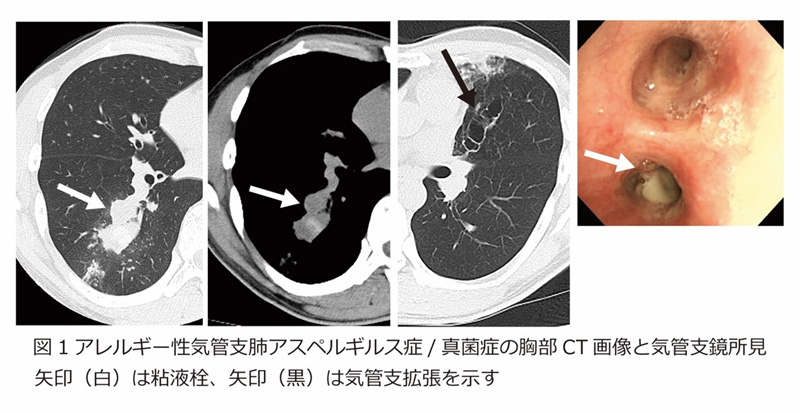

胸部エックス線では肺炎とよく似た影が映ることがあり、胸部CTでは気管支が粘液栓で詰まっている様子や、気管支の拡張がみられることがあります(図1)。また、血液検査でアスペルギルスに対するアレルギー反応の有無を調べ、喀痰検査などと組み合わせて診断を確定します。場合によっては気管支鏡検査を行い、詰まった痰を採取して詳しく調べることもあります。

図1